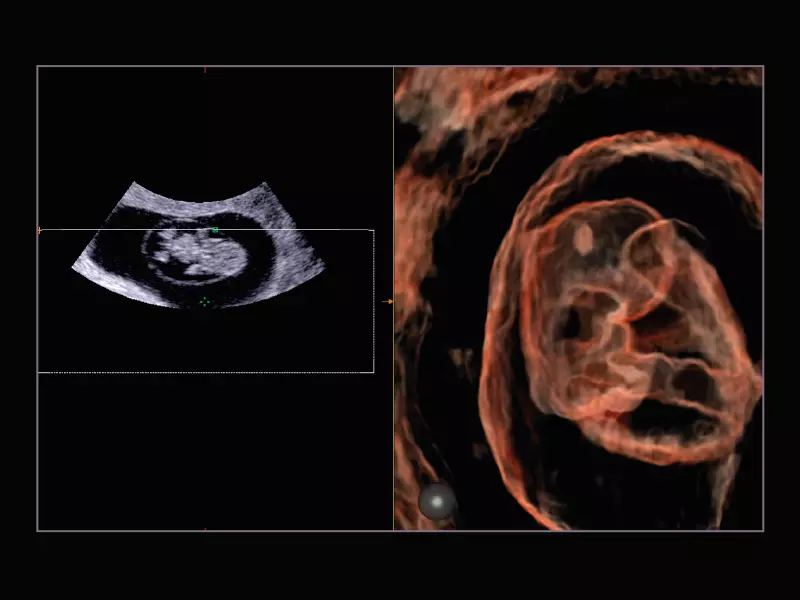

MyLab™9 Platform - Real-time baby face with 4D imaging

MyLab™9 Platform - Real-time baby face with 4D imaging

MyLab™9 Platform - Baby Face rendering in real-time with XLight

MyLab™9 Platform - Baby Face rendering in real-time with XLight